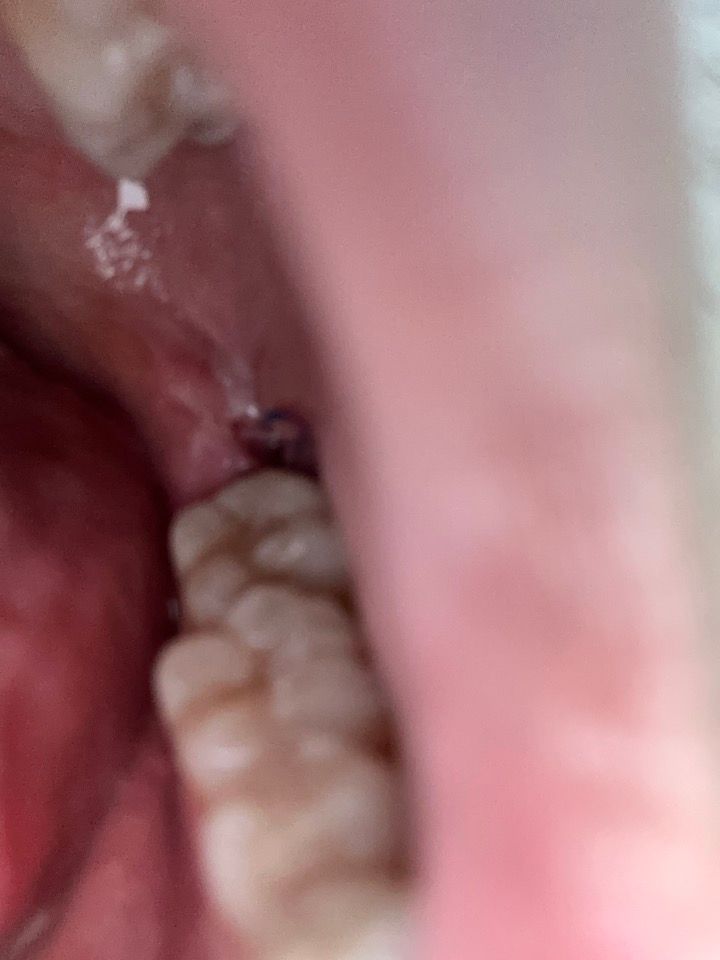

사랑니 발치 2일차인데 괜찮은 건가요?

발치 2일차 음주, 흡연, 빨대 아무것도 안했는데 갑자기 이 근처에 구멍이 생긴거 같기두해서 걱정되서 여쭤봅니다. 그냥 원래부터 이랬나 싶기도 하고 오늘 생긴거같기도 하고.... 괜찮은건가요? 통증은 전날보다 나아졌습니다.

혹시 혈병이 탈락된 걸까요?? 드라이소켓인지 여부도 궁금합니다..

크게 문제가 잇는건 아닌거 같습니다. 붓기가 빠지면서 저렇게 보이는거니 걱정하지 않으셔도 될것같습니다.

혈병이 제거된것은 맞으나 드라이 소켓이 생긴것 같지는 않아 보입니다.

사진상 드라이소켓이 생긴것으로 보이지는 않으며, 잘 아물고 있는 것으로 보입니다. 염증이 덧나지 않도록 소독용 헥사메딘 가글액으로 가글하여 관리하여주길 권합니다.

사진에서 염증 등의 문제가 될 만한 모습은 보이지 않습니다. 혈병은 외부에 붙어있을 필요 없습니다.

혈병은 발치 후 24시간 후 정도면 사라지고 이제 잇몸 재생을 시작합니다 완전히 발치 공간이 차오르려면 1~2달 이상 걸립니다